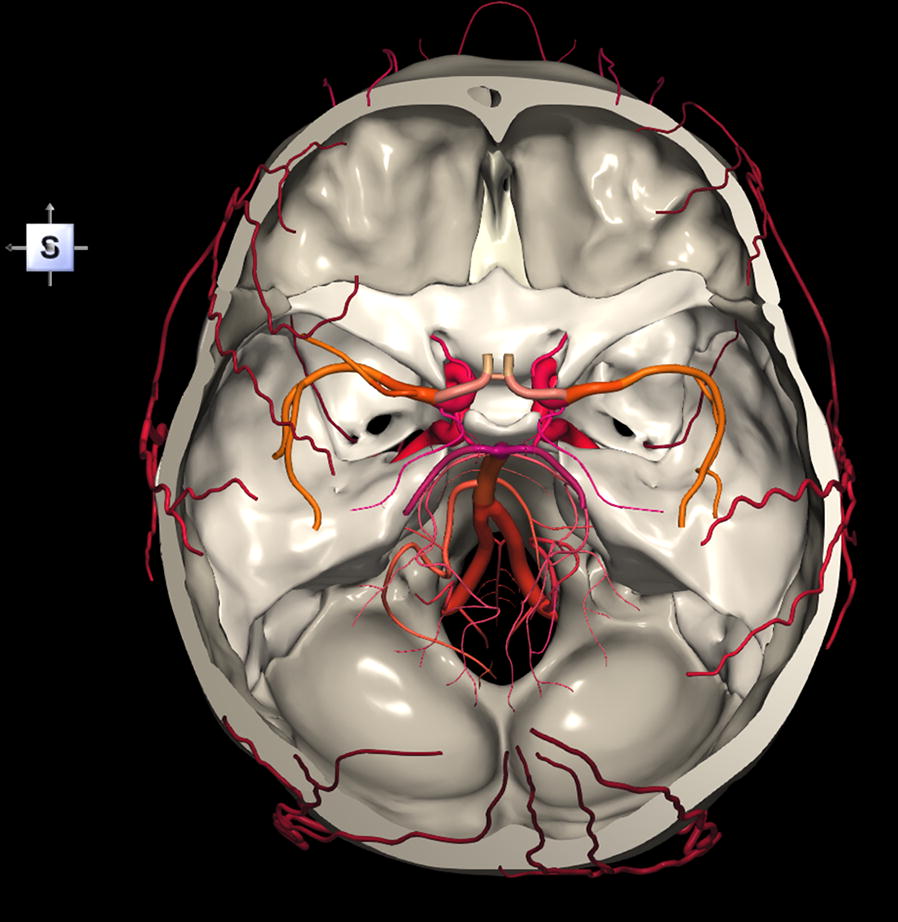

Ct is the modality of choice in defining the bony anatomy of the skull base and to depict the thin cortical margins of skull base neurovascular foramina. An interactive program for learning skull base anatomy welcome to navigating the skull base.

Ct skull base anatomy. You can however go directly to any section using the links below. B axial ct image with color coded overlay shows the skull base bones. The skull base can be evaluated by computed tomography ct which will demonstrate the bony structures of the skull base with its foramina and fissures for vessels and cranial nerves the temporal bone and sinonasal cavities.

The base of the skull is perforated by numerous foramina which allow vessels and nerves to pass through the base of the skull allowing the intracranial cavity to communicate with the rest of the body see main article. Skull ct anatomy the sagittal suture is the line where the right and left parietal bone are in contact. A noncontrast sinus or skull base ct which covers the mastoids temporal bone and entire skull base is recommended and intravenous contrast is not usually necessary as the mri will provide soft tissue detail.